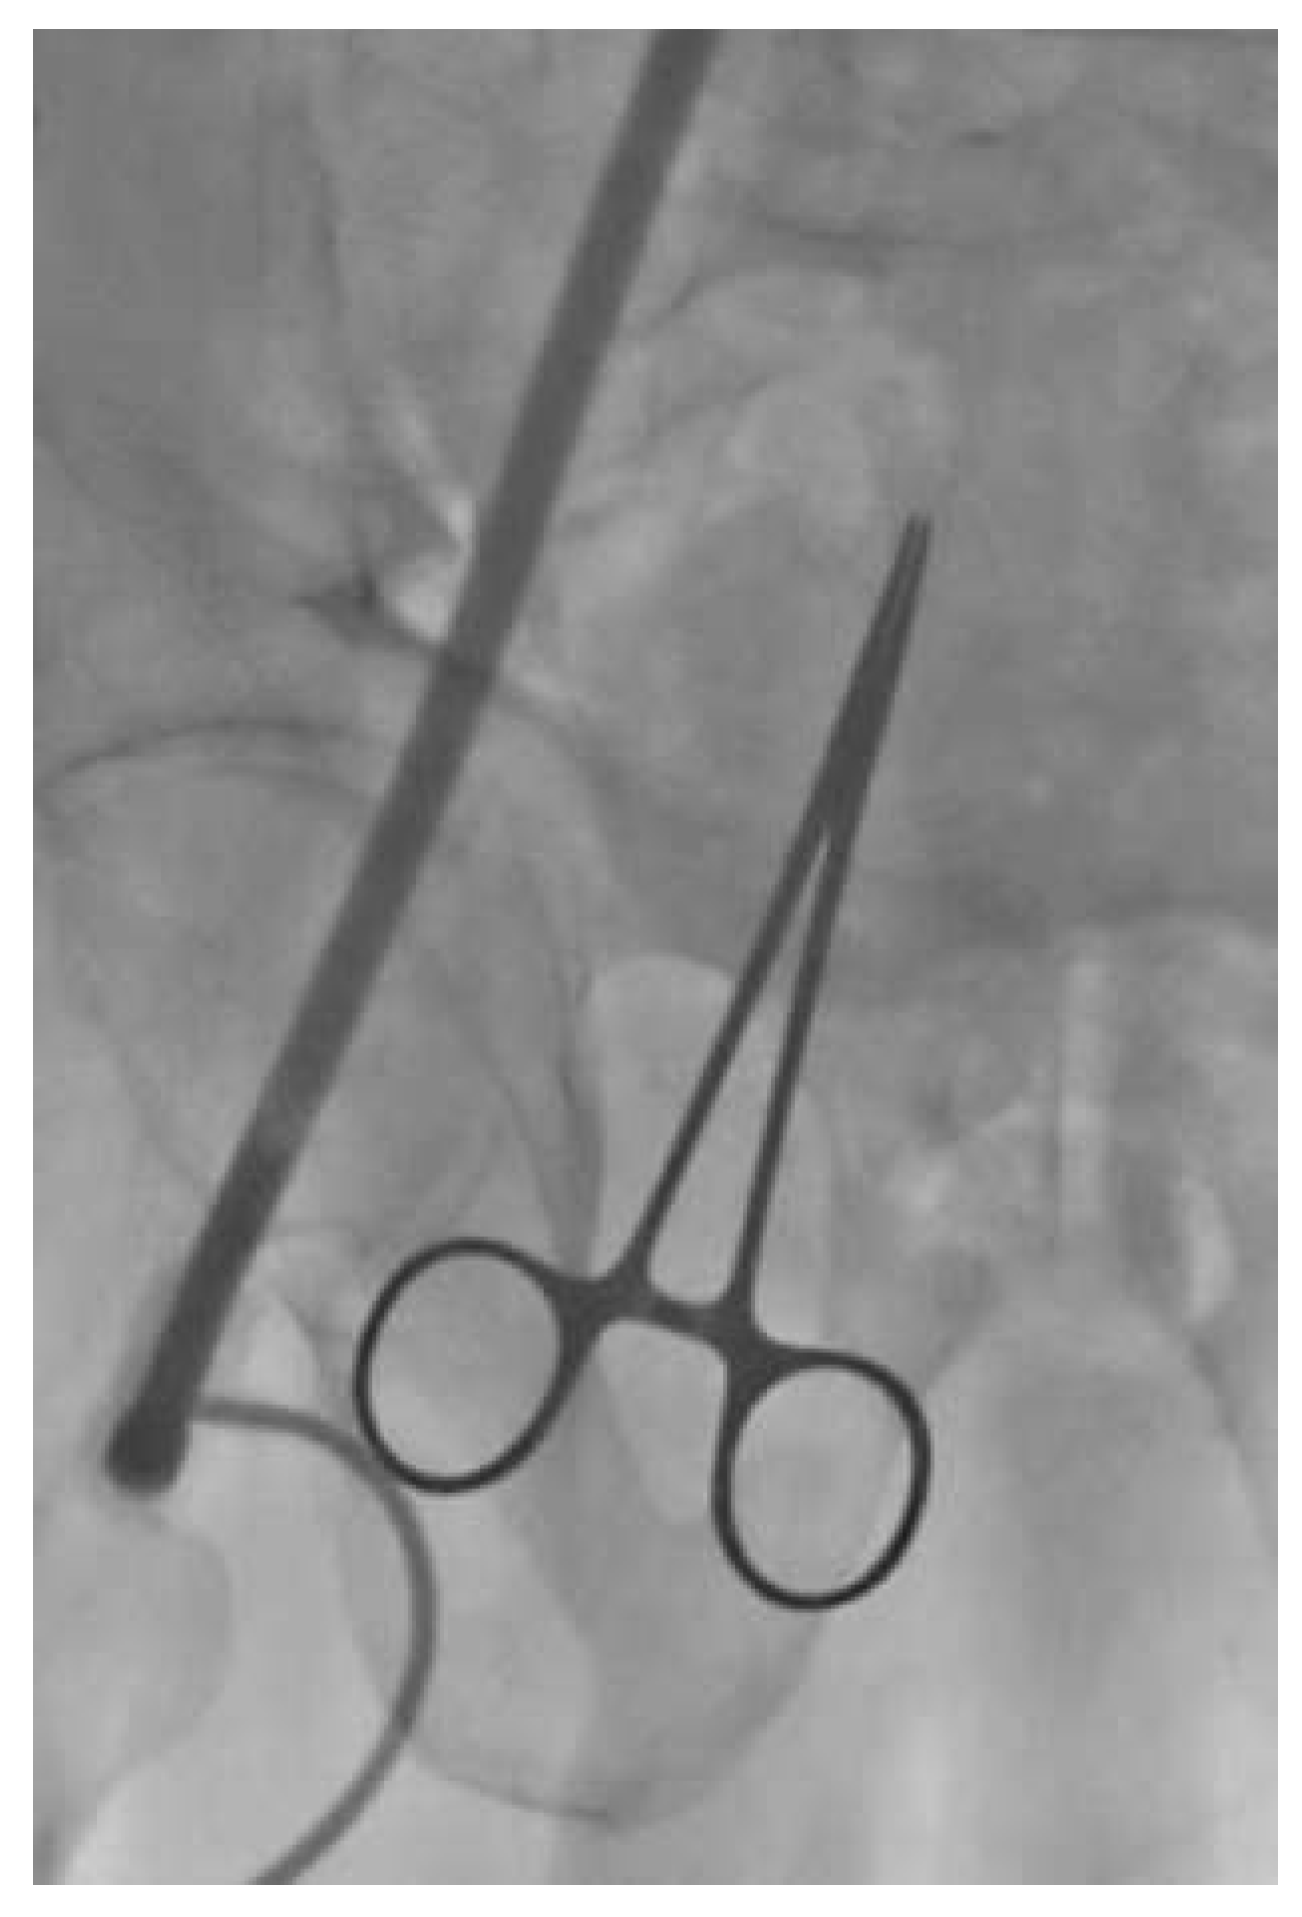

Under local anaesthesia and conscious sedation, we punctured the common femoral artery and performed the pre-closure technique using the Prostar® XL10 (Abbott Vascular, Reedwood City, CA). Over a Super Stiff ST-1 wire (Boston Scientific, Maple Grove, MN, USA) we inserted a folded 19-French SoloPath® sheath without any difficulties. As recommended by the instructions for use, once the sheath was full inserted we inflated the sheath balloon at 20 atmospheres for one minute. As we commonly did with other large-bore sheaths, the stiff wire was retrieved simultaneously with the dilator. At this time we noticed a kink in the sheath at the level of the iliac tortuosity (Figure 3), this kink was overcome with some difficulty by advancing a 0.035” wire. Subsequently, the kinked portion of the sheath was dilated with a peripheral balloon catheter (Admiral Xtreme 7 × 40 mm; Medtronic, MN, USA) (Figure 4). However, since we were not satisfied with that aspect of the sheath and we feared difficulties in advancement or retrieval of equipment during the procedure, we preferred to exchange the SoloPath® sheath for an 18-F Cook sheath (Cook Medical, Bloomington, IN, USA), which completely straightened the vessel (Figure 5). The procedure was then completed by pre-dilatation and successful implantation of a 29 Medtronic CoreValve®. The final ilio-femoral angiography from the contralateral femoral access showed no vascular complication or bleeding.

Figure 4. Admiral Xtreme 7 × 40 mm (Medtronic) balloon inflated in the SoloPath® sheath.